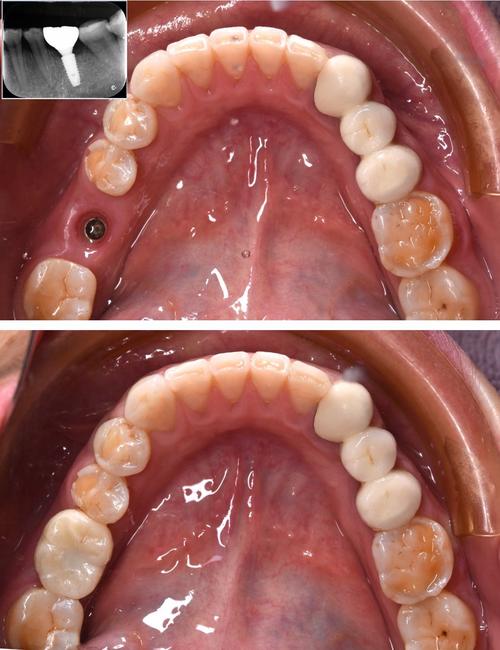

- 基台连接与取模:

- 骨结合完成后,进行二次小手术(或微创方式)暴露种植体顶部,连接愈合基台(引导牙龈成型)。

- 待牙龈形态稳定后,更换最终基台,并取模(或口内扫描)用于制作牙冠。

- 牙冠制作与佩戴:

- 技工所根据模型制作牙冠(烤瓷冠或全瓷冠)。

- 试戴牙冠,检查颜色、形态、咬合关系是否合适。

- 粘固牙冠,完成最终修复。